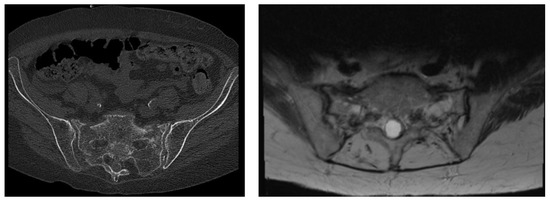

2. Materials and Methods